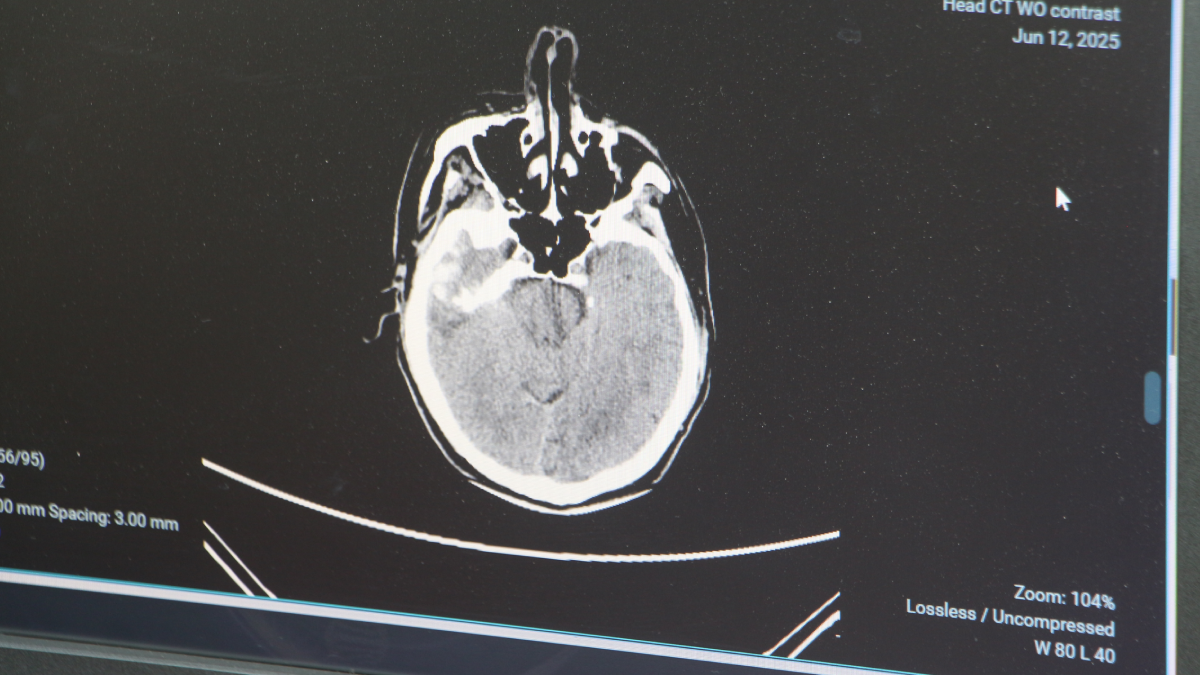

Genellikle 50 yaştan sonra görülen beyin kanaması, son yıllarda gençlerde daha sık görülmeye başlandı. Sebeplerine dikkati çeken Adana Şehir Hastanesi Beyin ve Sinir Cerrahisi Bölümü’nden Doç. Dr. Ali İhsan Ökten, bunların daha çok ‘arteriyovenöz malformasyon’ ve ‘anevrizma’ kaynaklı yaşandığını söyledi. Anevrizma, yani kan damarlarının duvarında oluşan baloncuk şeklindeki patolojik genişlemeler kaynaklı yaşanan beyin kanamalarının 100 binde 10 ile 15 kişi arasında görüldüğünü dile getiren Doç. Dr. Ali İhsan Ökten, “Gençlerde görülme oranı giderek artıyor” dedi.